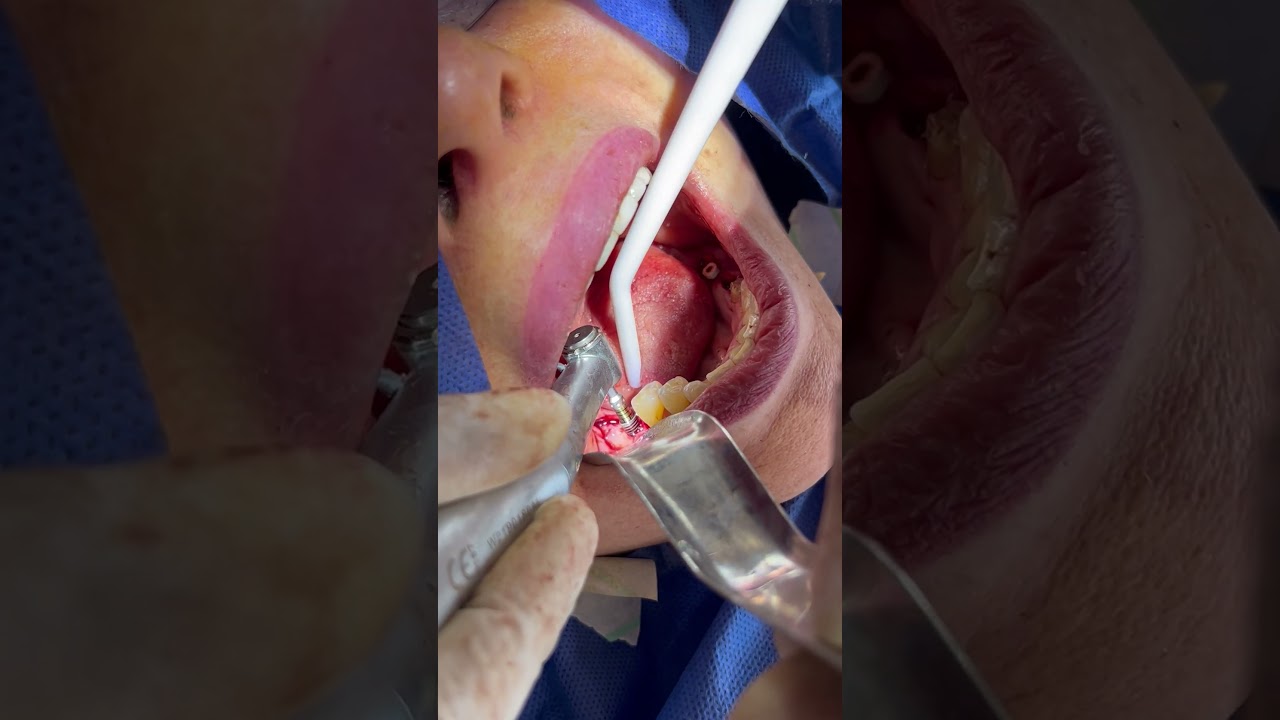

¿Que es un Implante Dental?

- Es un aditamento con forma de tornillo elaborado de titanio o de zirconio, que se inserta en el hueso a través de una pequeña cirugía, hasta que se osteointegre con el hueso y se coloque un provisional y posteriormente una corona definitiva.

-La ventaja de los Implantes Dentales es que sustituyen a los dientes o muelas perdidos sin que se tenga que desgastar los dientes adyacentes para un puente fijo.